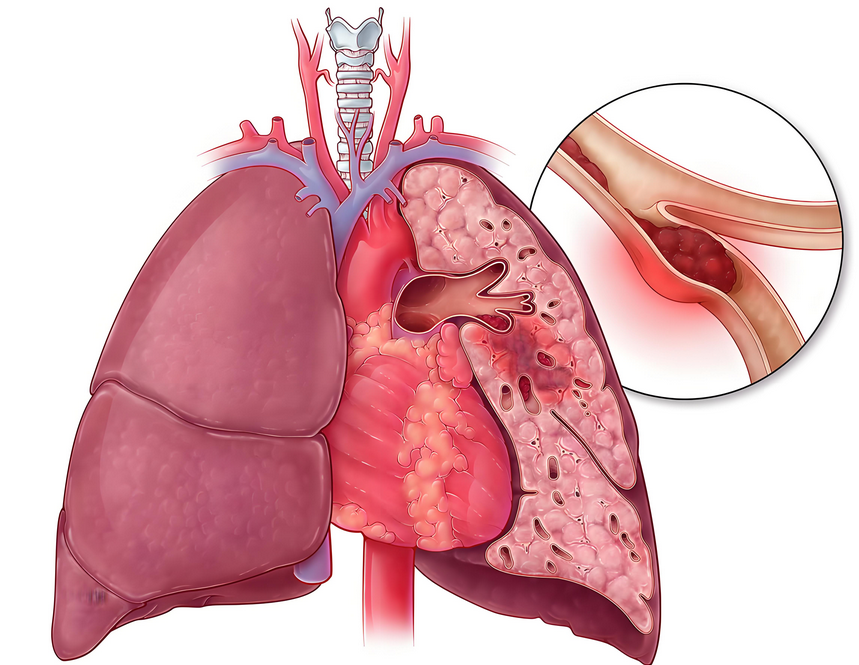

肺动脉栓塞(Pulmonary Embolism, PE),并非罕见的疾病。它通常源于下肢或盆腔深静脉的血栓脱落,随血流“漂流”至肺动脉,造成血管堵塞。其起病急、进展快、死亡率极高,堪称“心血管领域的幽灵”。患者常表现为突发的呼吸困难、剧烈胸痛、咯血、晕厥等。但由于这些症状缺乏特异性,极易被误诊为心肌梗死、主动脉夹层或其他疾病。很多患者在确诊前便已遭遇不测,因此,它又被称为“沉默的杀手”。